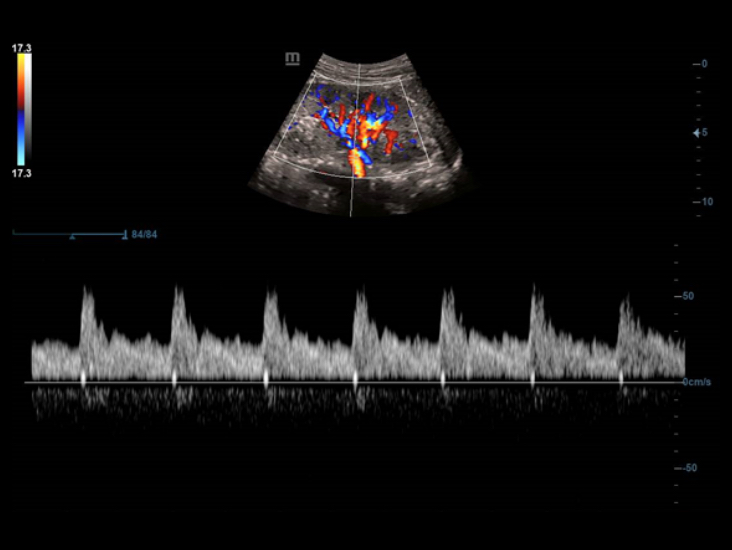

Smart Track biedt snelle en intelligente optimalisatie voor vasculaire beeldvorming met slechts ├®├®n druk op de knop. Het optimaliseert het kleuren-, power- en PW-spectrum met zelftracking en reduceert het aantal tijdrovende stappen. De workflow voor vasculair onderzoek wordt daarmee vereenvoudigd met een optimale weergave.